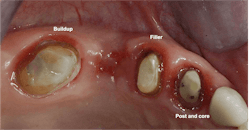

My suggestions are based on the dental literature and my many years of practice experience. Consider the factors below to help you decide whether pins or posts are needed. Figures 1–3 show the need for the restorative buildup procedures.

Quantity of tooth structure remaining

A general rule to determine if a tooth needs a buildup is related to how much coronal tooth structure is not present. If one-half or more of the coronal tooth structure is missing and most of the remaining tooth is dentin only, placing a buildup is advised. If a buildup is needed, frequently pins should be placed to provide long-term retention of the material to the dentin. Additionally, most agree that about 2 mm of near-parallel tooth structure should be remaining circumferentially coronal to the prep margin to provide a ferrule effect for retention.

Retentive pins can be made of stainless steel (nickel), titanium alloy, or pure titanium. All three have successful clinical research in the literature to support their use. Pure titanium pins provide adequate retention and develop fewer cracks in the remaining tooth structure. Example brands are Nordin, Filpin, and Stabilok. Retentive pins are usually placed approximately 2 mm into tooth structure at an angle of 15 or 20 degrees from the long axis of the tooth, and then bent over into the long axis of the tooth. Usually, one pin is placed on each corner of the tooth where the tooth structure is missing. This technique provides long-term retention of the buildup material.